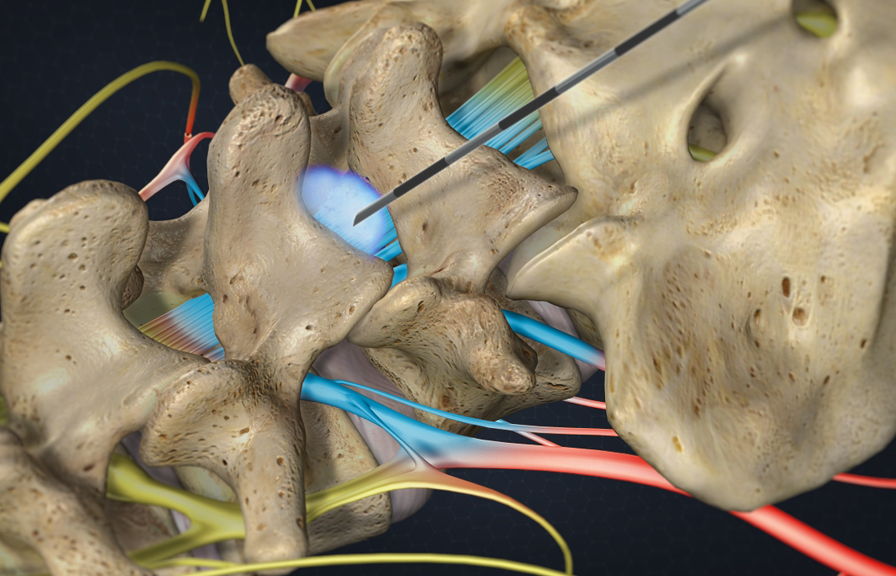

Have you had a back or neck surgery? Do you still have pain? If you suffer from chronic pain due to:

- Failed back surgery

- Spinal Stenosis

- Pinched Nerves

- Sciatica